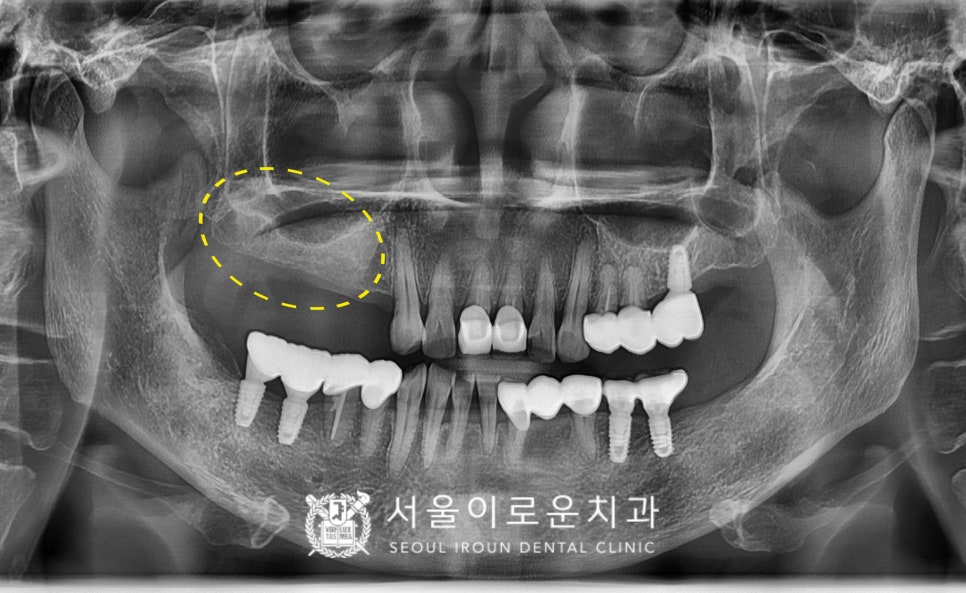

자연치아와 강도가 가장 유사하고

심미적인 지르코니아 크라운으로

보철을 마무리해드린 치료 후 모습입니다!

환.자분께서는

타원에서 아래턱 임플란트 진행 시

많이 아프고 불편하셔서

걱정을 많이 했었는데

통.증도 거의 없고

출혈도 잘 멎어서 만.족하셨으며

양측으로 편안한 식사가 가능하셔서

정말 좋아해하셨답니다.

(2023.09.11ㅡ>2024.03.26)